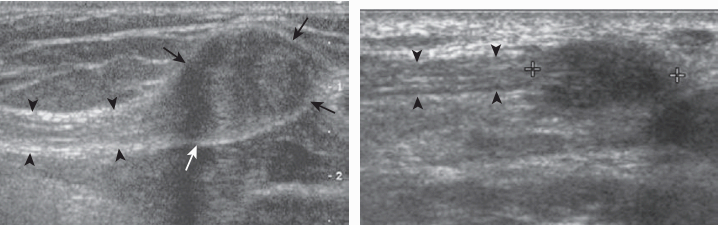

가로절단신경종(transection neuroma) 은 진성종양이 아니고, 절단된 신경이 재생되는 과정에 생기며, 신경섬유와 흉터조직이 섞여있다. 초음파에서 불균질 하며 대부분 낮은 에코 덩어리로 보인다.

가로절단신경종(transection neuroma) 초음파소견은 비특이적이지만 덩어리와 말초신경 간의 연결성을 확인할 수 있다. 말초신경이 신경종 내로 들어가는 부분은 대개 낮은 에코로 보이기 때문에 진단에 도움이 된다. 가로절단신경종은 색 및 강화도플러 영사에서 다양한 혈류를 보인다. 가로절단신경종은 절단된 신경에서 생길 수 있다는 점을 예측하는 것이 진단에 중요하다. 신경종위에 탐촉자를 직접 압박하면 특징적인 증상을 유발하는 부위를 정확하게 알 수 있으며, 자기 공명영상(MRI)과 비교하여 초음파가 지니는 장점이다.